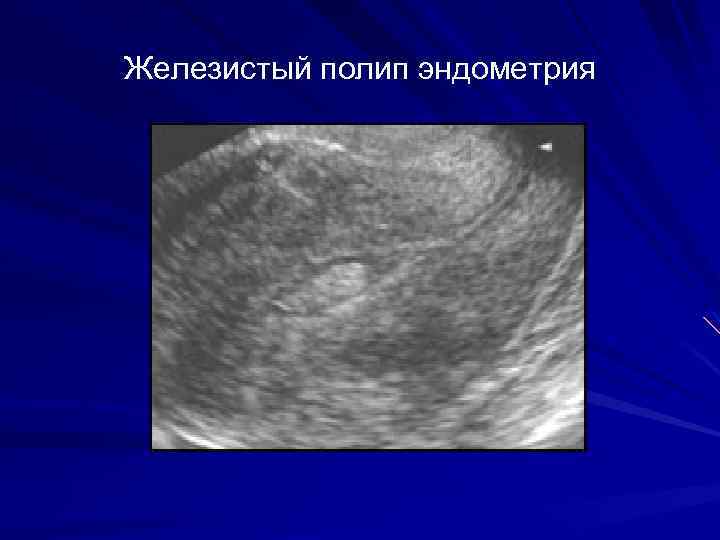

Медицинская диагностика: Гиперплазия эндометрия на УЗИ